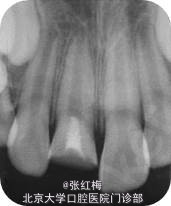

X线示:11、21发育9期,根管粗大,未见明显根折线,根尖周未见病变影,骨硬板清晰,未见牙槽突骨折线;

检查:11充填体完好,叩(-),不松,龈未见异常,X线:11根尖继续形成中,根周膜清 晰;

检查:11粘接断冠完好,叩(-),不松,龈未见异常,冷测有感觉,无疼痛;X线:11根 尖继续

形成中,根周膜清晰